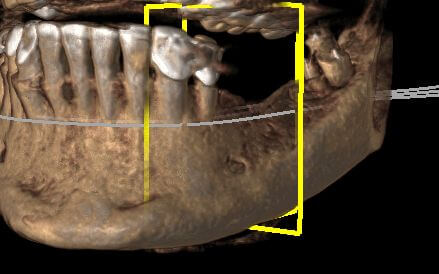

Пациентку не устраивал съемный протез нижней челюсти, который она носила на протяжении нескольких лет. У пациентки на нижней челюсти отмечался выраженный дефицит костной ткани как по высоте, так и по ширине. Без предварительной костной пластики установка имплантатов для несъемной конструкции невозможна. Выполнена костная пластика титановой сеткой.

По контрольной рентгенограмме прирост кости по ширине и высоте. Планируется вторым этапом имплантация на нижней челюсти.